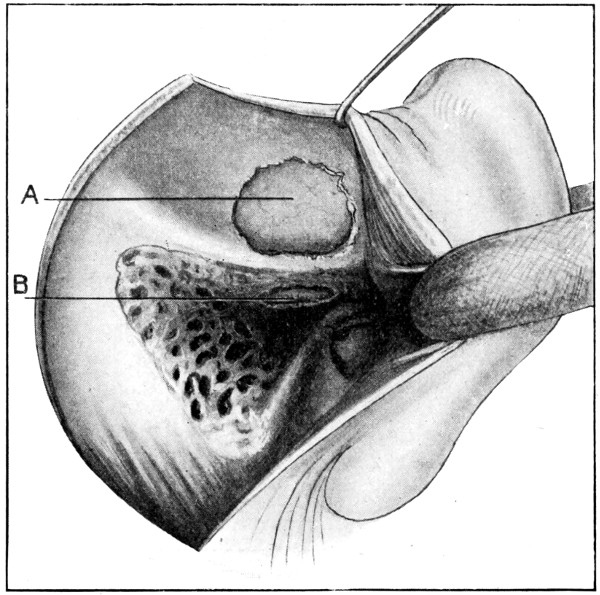

75. A large right-sided temporo-sphenoidal abscess 256

76. To illustrate the pressure effects of a temporo-sphenoidal abscess 257

79. The exposure of a temporo-sphenoidal abscess 265

80. The ‘radical’ mastoid operation (after Hunter Tod) 269

81. Exploration for a temporo-sphenoidal abscess (after Hunter Tod) 270

82. Exploration for a cerebellar abscess (after Hunter Tod) 271

83. A fracture of the anterior fossa which was followed by the development of meningitis 275

84. Basal meningitis secondary to temporo-sphenoidal abscess 277

85 A and B. To illustrate the exposure of the lateral sinus (after Hunter Tod) 285

86. A case of Hernia cerebri and the abscess after removal 292